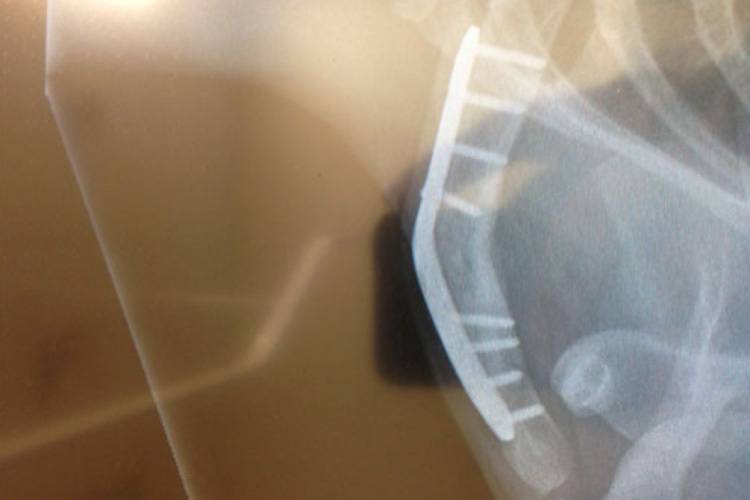

Beim vierten und letzten EM-Finale in Rzeszow am kommenden Sonntag (ab 19 Uhr live auf Eurosport) steht Woffinden nach wie vor auf der Startliste, doch er wird nicht fahren. "Beim meinem Sturz in Stockholm hat es die Metallplatte am Schlüsselbein verbogen, die Platte hält den Knochen aber nach wie vor zusammen", erklärte der WM-Leader. "Ich werde die kommende Woche ausruhen und erst in Thorn wieder fahren. Nach dem Rennen gehe ich erneut zum Arzt. Dann entscheiden wir, wie es weitergeht."